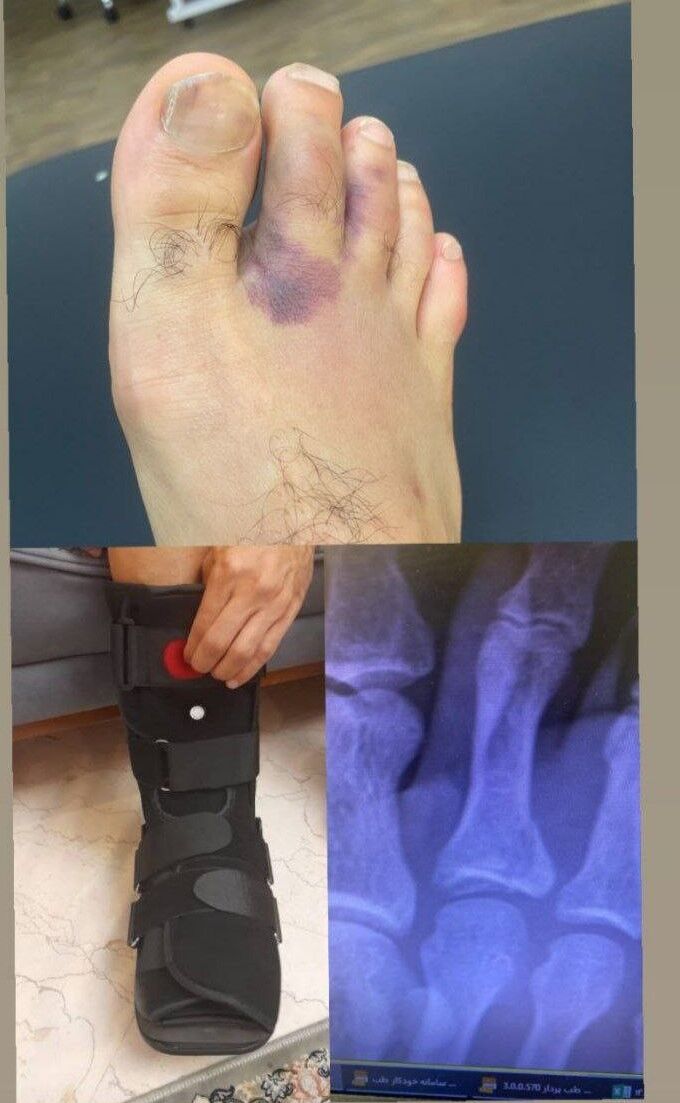

روزنو :با انتشار تصویری در فضای مجازی، شدت مصدومیت امید عالیشاه مشخص شد.

امروز عکسی از شکستگی پای عالیشاه منتشر شد که نشان می دهد انگشت پای این بازیکن شکسته و قادر به همراهی تیم پرسپولیس نخواهد بود.